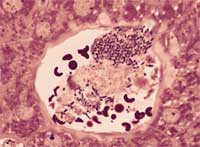

Salmonella pollurum gallinarum est responsable de ces 2 maladies. La pullorose qui affecte les jeunes poussins et la typhose qui affecte les adultes.